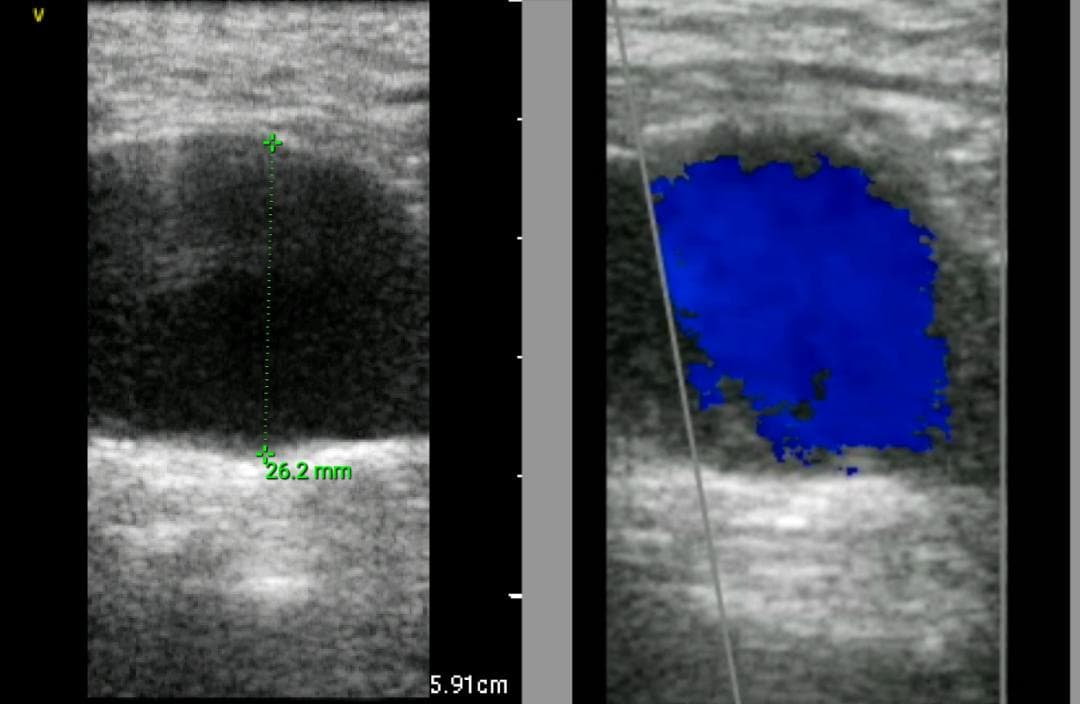

おわかりになる方のみの購入をお願いいたします実際に実施した写真をあげました正常肝臓、胆石症、頸動脈プラーク、同じく頸動脈プラーク、Mrの収縮期、同じくM弁の開放期とA弁の開放期、腹部大動脈瘤、正常の頸動脈、甲状腺右葉の結節、前立腺肥大画像の描出は条件によりますがご検討をお願いいたします経年変化、使用に伴うスレや傷などがあります機能に問題はありませんスキャンは心血管、腹部、体表に対応します外部接続端子のカバーが一部壊れていますが蓋は閉まりますバッテリーはフル充電されますが劣化はあると思います医療用モニタリング機器 Vscan Extend、GE- モデル名: Vscan Extend- ブランド: GE- 色: ホワイト- 機能: 医療用モニタリング機器ご覧いただきありがとうございます。。[新品未使用品]KT TAPE ブラック 25cm プレカット 150枚入